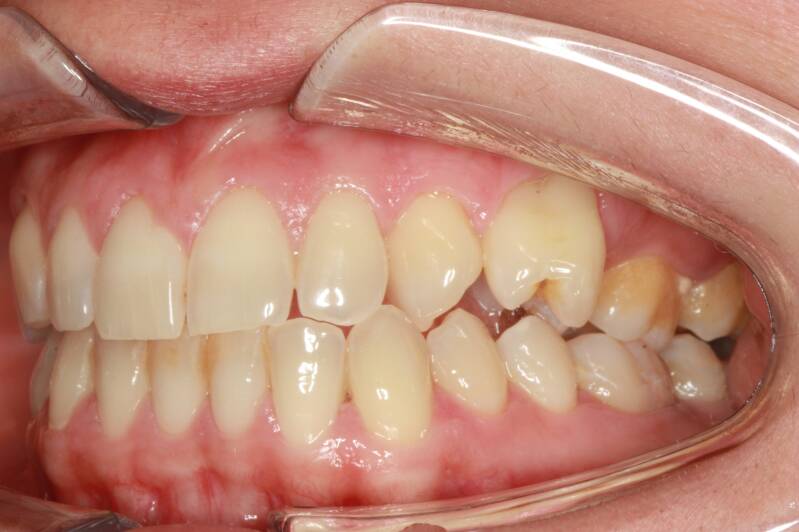

Questo mese vi presentiamo G.G. f. di15aa. Ha una seconda classe suddivisione destra molare e canina. richiesta Allineamento.

FOTO INIZIALI PRE TRATTAMENTO ORTODONTICO

PRIMA CLASSE CON AFFOLLAMENTO GRAVE SUPERIORE A SINISTRA CON PERDITA PRECOCE DEL SECONDO MOLARE INFERIORE SINISTRO

Abbiamo appena portato a termine questo caso che presentava in arcata superiore il primo premolare di sinistra completamente fuori arcata sovrapposto al secondo premolare ed il canino ruotato.

in arcata inferiore invece abbiamo estratto il secondo molare di sinistra perso per carie deostruente e mesializzato il terzo molare in modo da chiudere lo spazio e non ricorrere all'inserimento di protesi implantare.